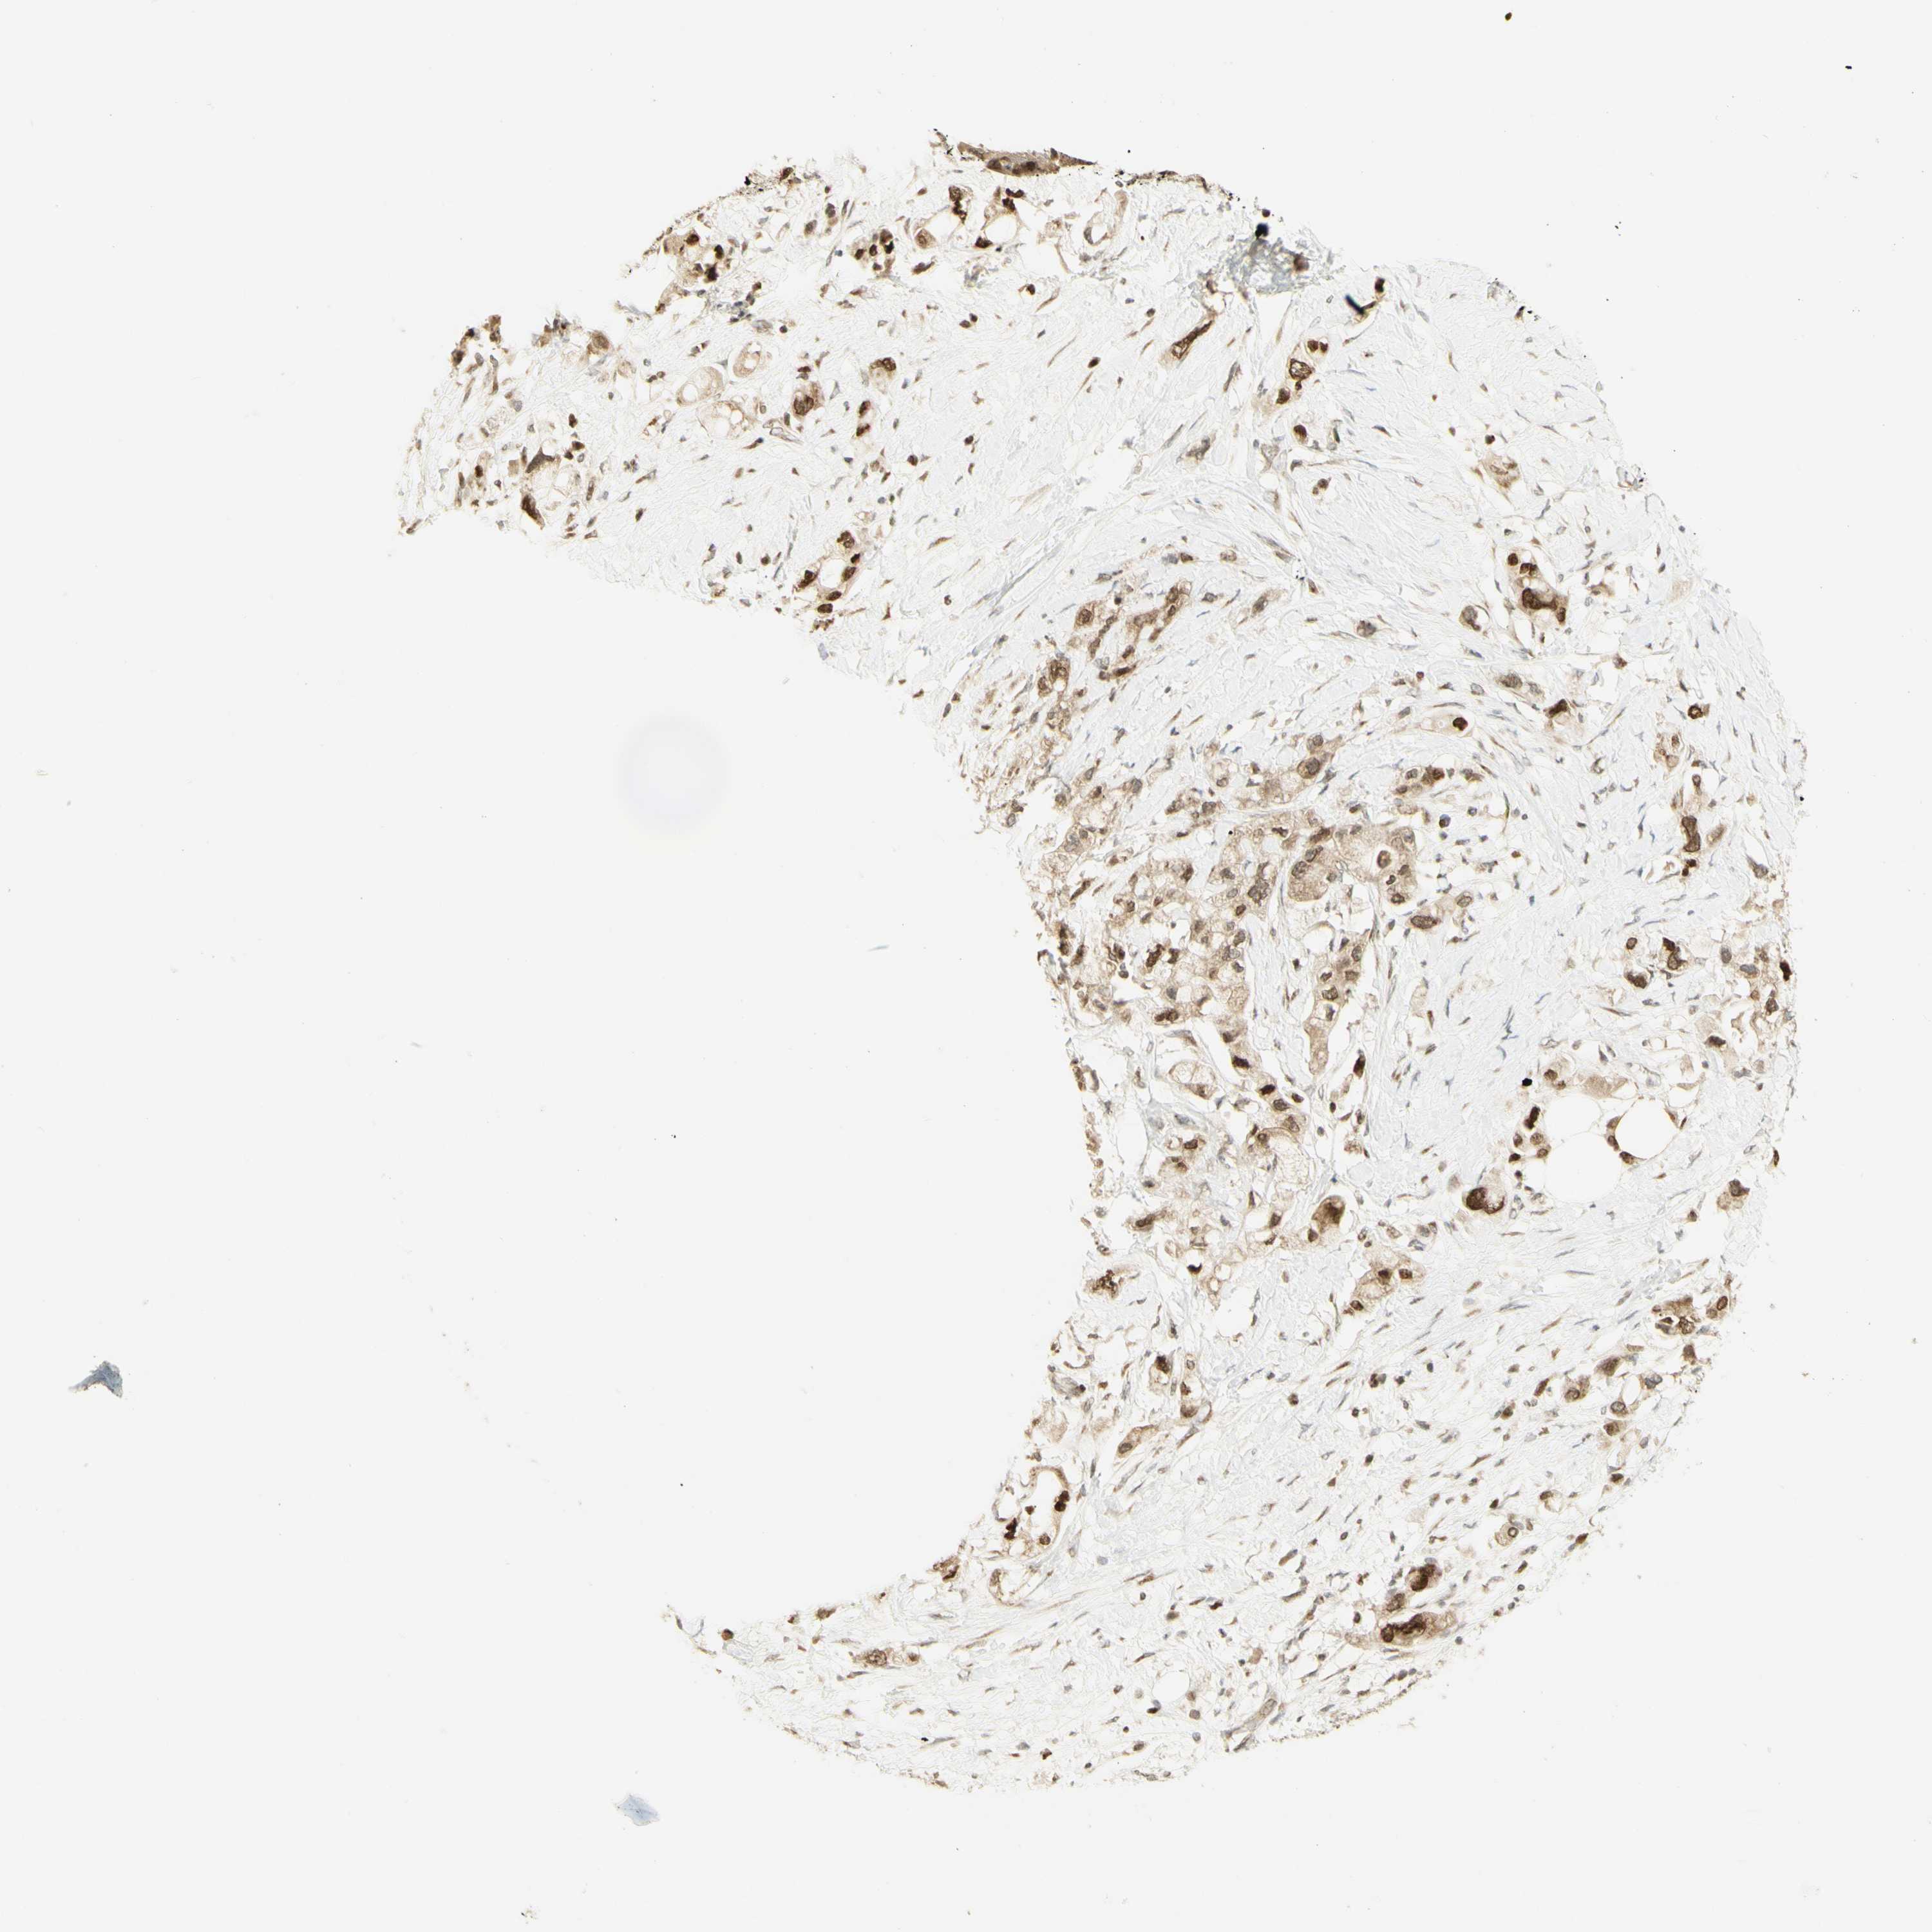

PANCREATIC CANCER - Protein expressioni

A mouse-over function shows sample information and annotation data. Click on an image to view it in a full screen mode. Samples can be filtered based on level of antibody staining by selecting one or several of the following categories: high, medium, low and not detected. The assay and annotation is described here.

Note that samples used for immunohistochemistry by the Human Protein Atlas do not correspond to samples in the TCGA dataset.

Antibody stainingi

Antibody staining in the annotated cell types in the current human tissue is reported as not detected, low, medium, or high, based on conventional immunohistochemistry profiling in selected tissues. This score is based on the combination of the staining intensity and fraction of stained cells.

Each image is clickable and will lead to virtual microscopy that enables deeper exploration of all samples and also displays staining intensity scores, fraction scores and subcellular localization as well as patient and tissue information for each sample.

Antibody HPA006916

Antibody HPA010568

Antibody CAB017617

Staining

High

Medium

Low

Not detected

Intensity

Strong

Moderate

Weak

Negative

Quantity

>75%

75%-25%

<25%

None

Location

Nuclear

Cytoplasmic/membranous

Cytoplasmic/membranous,nuclear

Adenocarcinoma, NOS

Adenocarcinoma, metastatic, NOS